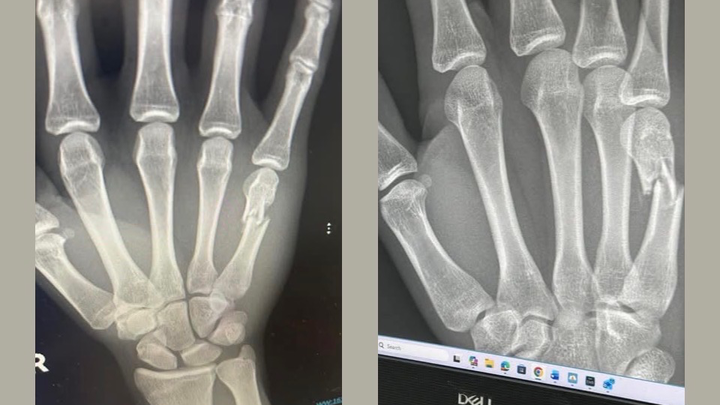

Two weeks ago I broke my hand and the following week I found out that the bone I broke is now shifting and I am in need of surgery. Or it will not heal right

In order to go to the military. I need to have surgery and be medically cleared if I do not get the surgery, the military is out though question because they are saying that it will heal wrong and I won’t have full motion in my hands, nor will I be able to grip things properly.